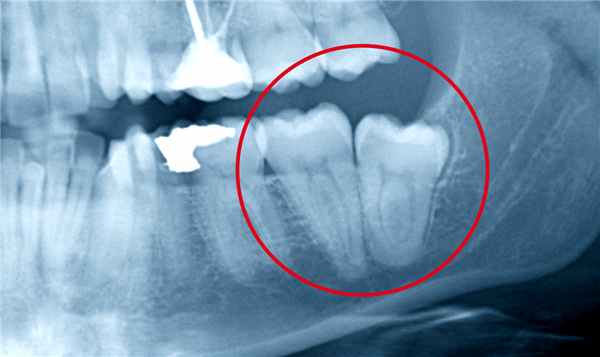

Ведущая роль в диагностике анкилоза принадлежит рентгенологическому исследованию. Оно базируется на оценке функциональных рентгенограмм - томограмм или зонограмм, которые выполняют в различных положениях нижней челюсти (обычно с широко открытым ртом и в обычной окклюзии).

Рентгенологические признаки фиброзного анкилоза:

- суставная щель едва заметна;

- суставная головка уплощена, шейка утолщена.

Рентгенологические признаки костного анкилоза:

- полное исчезновение суставной щели;

- костное сращение головки нижней челюсти с суставным углублением височной кости;

- образования единого костного конгломерата, в который может входить скуловая дуга;

- утолщение и укорочение шейки нижней челюсти.

При проведении ортопантомографии, рентгенографии или компьютерной томографии ВНЧС обнаруживаются рентгенологические признаки анкилоза: частичное либо полное отсутствие суставной щели, разрушение головки сустава, деформация и укорочение ветви нижней челюсти и др. При необходимости обследование дополняется КЛКТ ВНЧС, контрастной артрографией, электромиографией. Для оценки прикуса и окклюзионных контактов производится изготовление и анализ диагностических моделей челюстей.

При этой форме анкилоза пациент не может полностью открыть рот. Со временем делать это становится больному все сложнее. Из-за формирования фиброзной ткани на рентгеновском снимке суставная щель просматривается нечетко и выглядит прерывистой.

Костный анкилоз

При костном анкилозе ВНЧС имеет место соединение мыщелкового отростка со скуловой дугой. Получается, что костная ткань наполняет собой полость сустава. Костный анкилоз ВНЧС бывает частичным или полным, это зависит от того, остались ли нетронутые места на поверхности суставов. Если болезнь поражает только один сустав, лицо становится несимметричным. При поражении двух суставов верхняя челюсть сдвигается вперед, происходит ниспадание подбородочного отдела, что приводит к нарушению прикуса и проблемам с зубами, речью и дыханием. Человеку с таким недугом будет трудно принимать твердую пищу. Полная форма характеризуется тем, что на рентгеновском снимке суставная щель не просматривается, а мыщелковый отросток выглядит более широким, чем должен.